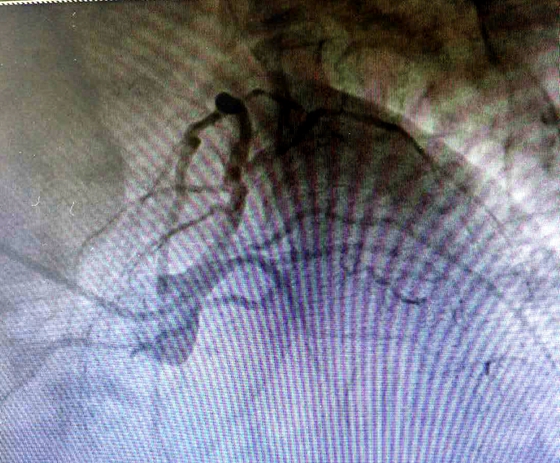

近来,李某因胸闷胸痛症状明显加重,前来湘雅常德医院心血管内科就诊,完善冠脉造影检查提示:前降支开口狭窄80%,近中段弥漫性狭窄75%-95%,伴严重钙化,远段狭窄50%;回旋支开口至近段75%-90%,中段完全闭塞;右冠细小,近段狭窄50%,中远段50%-70%。

完善术前准备后,特邀中南大学湘雅三医院曹宇教授与湘雅常德医院彭道地主任、范爱德主任医师携手,带领介入团队在IABP支持下,辅以IVUS检查,行冠脉旋磨术。旋磨成功以后,采用球囊预扩张,然后植入药物洗脱支架覆盖病变。手术治疗过程顺利,没有出现并发症。

术后复查造影示支架贴壁良好,支架内无狭窄,远端血流正常,手术顺利完成。